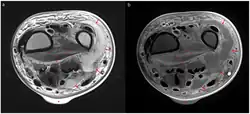

Magnetic resonance imaging (MRI)

Magnetic resonance imaging (MRI) is considered superior to computed tomography (CT) in the visualization of soft tissues and is able to detect about 93% of NF cases.[15] It is especially useful in finding fluid in the deep fascia, which can distinguish between NF and cellulitis.[15] When fluid collects in the deep fascia, or thickening or enhancement with contrast, necrotizing fasciitis should be strongly suspected. However, MRI is much slower than CT and not as widely available.[15] There may also be limitations on its use in patients with kidney problems.[15]